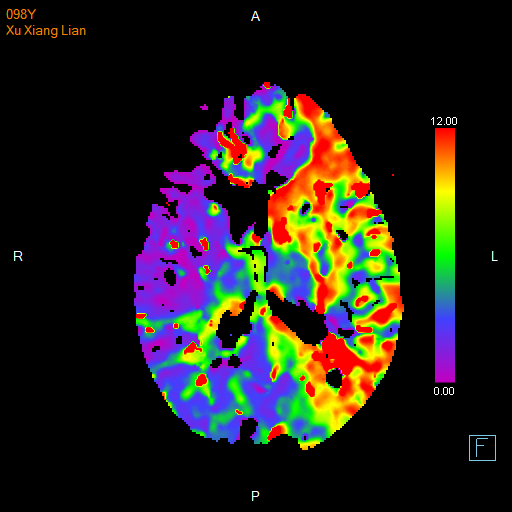

进一步的血管检查(CTA+CTP)发现了更严重的问题:王奶奶的左侧颈内动脉完全闭塞——这是脑梗中最凶险的类型之一,意味着大脑主要供血通道被切断,随时可能危及生命

颅脑 CTP

与家属充分沟通后,医疗团队决定迎难而上,为王奶奶实施了“取栓支架保护下脑动脉取栓术”,在一个小时内成功将堵塞在左侧颈内动脉及大脑中动脉的大量血栓取出,瞬间恢复了大脑供血。

急诊介入手术前后血管